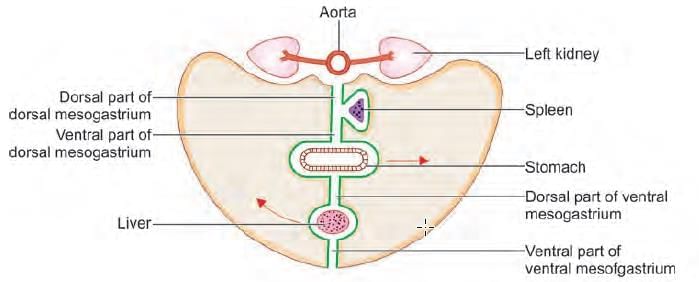

A 25-year-old male presents to emergency with left upper quadrant pain, upon examination spleen was measured to 20 cm and further extending to the mid umbilicus. The extension of the spleen to left lower quadrant was prevented by: (NEET-PG 2021)